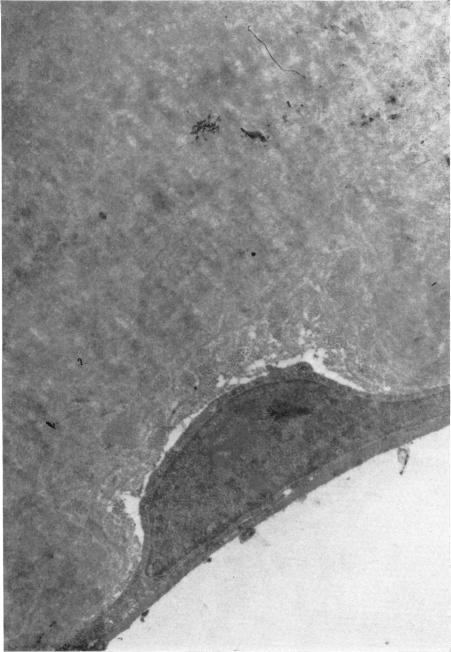

Hereditary deep dystrophy of the cornea (polymorphous).

Trans Am Ophthalmol Soc. 1969;67:235-64.